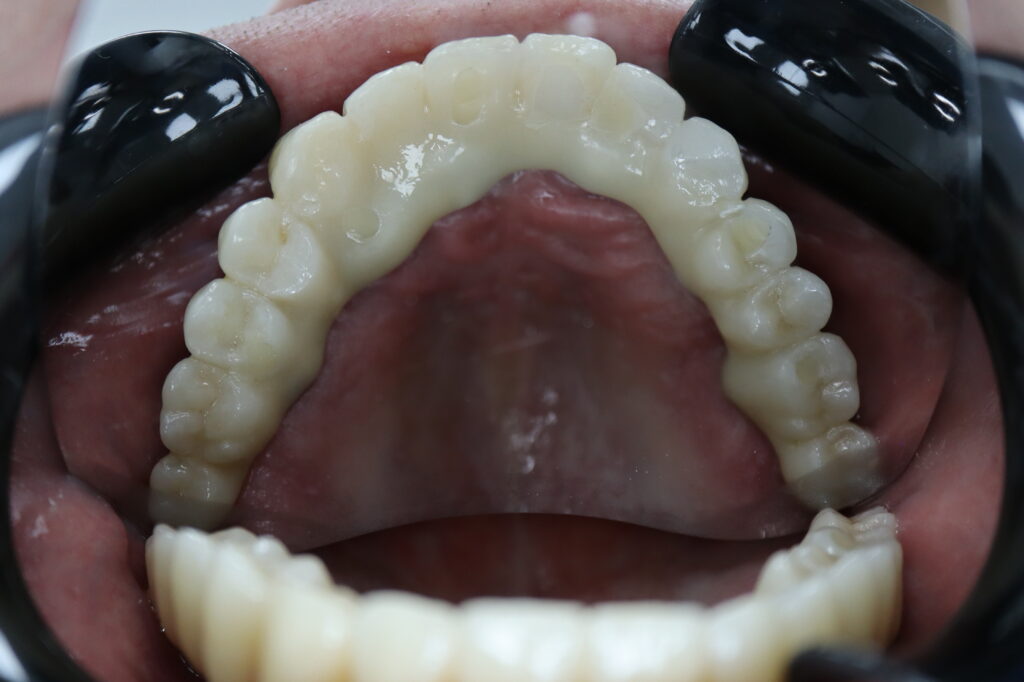

Пациент продолжает лечение спустя 3 месяца после имплантации и установки временного металлоакрилового протеза с опорой на 6-ти дентальных имплантантах Megagen Anyone.

Лечение начато с выбора материала для будущей конструкции (диоксид циркония на титановой балке) и цвета.

Был установлен временный протез из PMMA, максимально воссоздающий форму и цвет (А3) будущей конструкции.

Спустя 25 дней был зафиксирован протез с опопрой на дентальные имплантаты из диоксида циркония с армированием из титана.